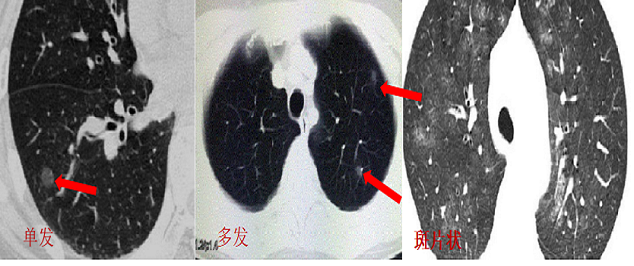

一、首先什么是肺结节

肺结节其实是医学上一类肺影像学表现的统称。其中最常见也是最重要的当属肺磨玻璃影(GGO,ground glass opacity)。GGO在胸部CT表现为密度轻度增高的云雾状淡薄影 / 圆形结节,样子像磨砂玻璃或者云朵的密度一样,所以叫磨玻璃影。(如下图红箭头所示)